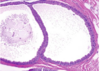

Q

A

BR; invasive ductal

BL: dcis

TR: invasive lobular

TL: insitu loblar